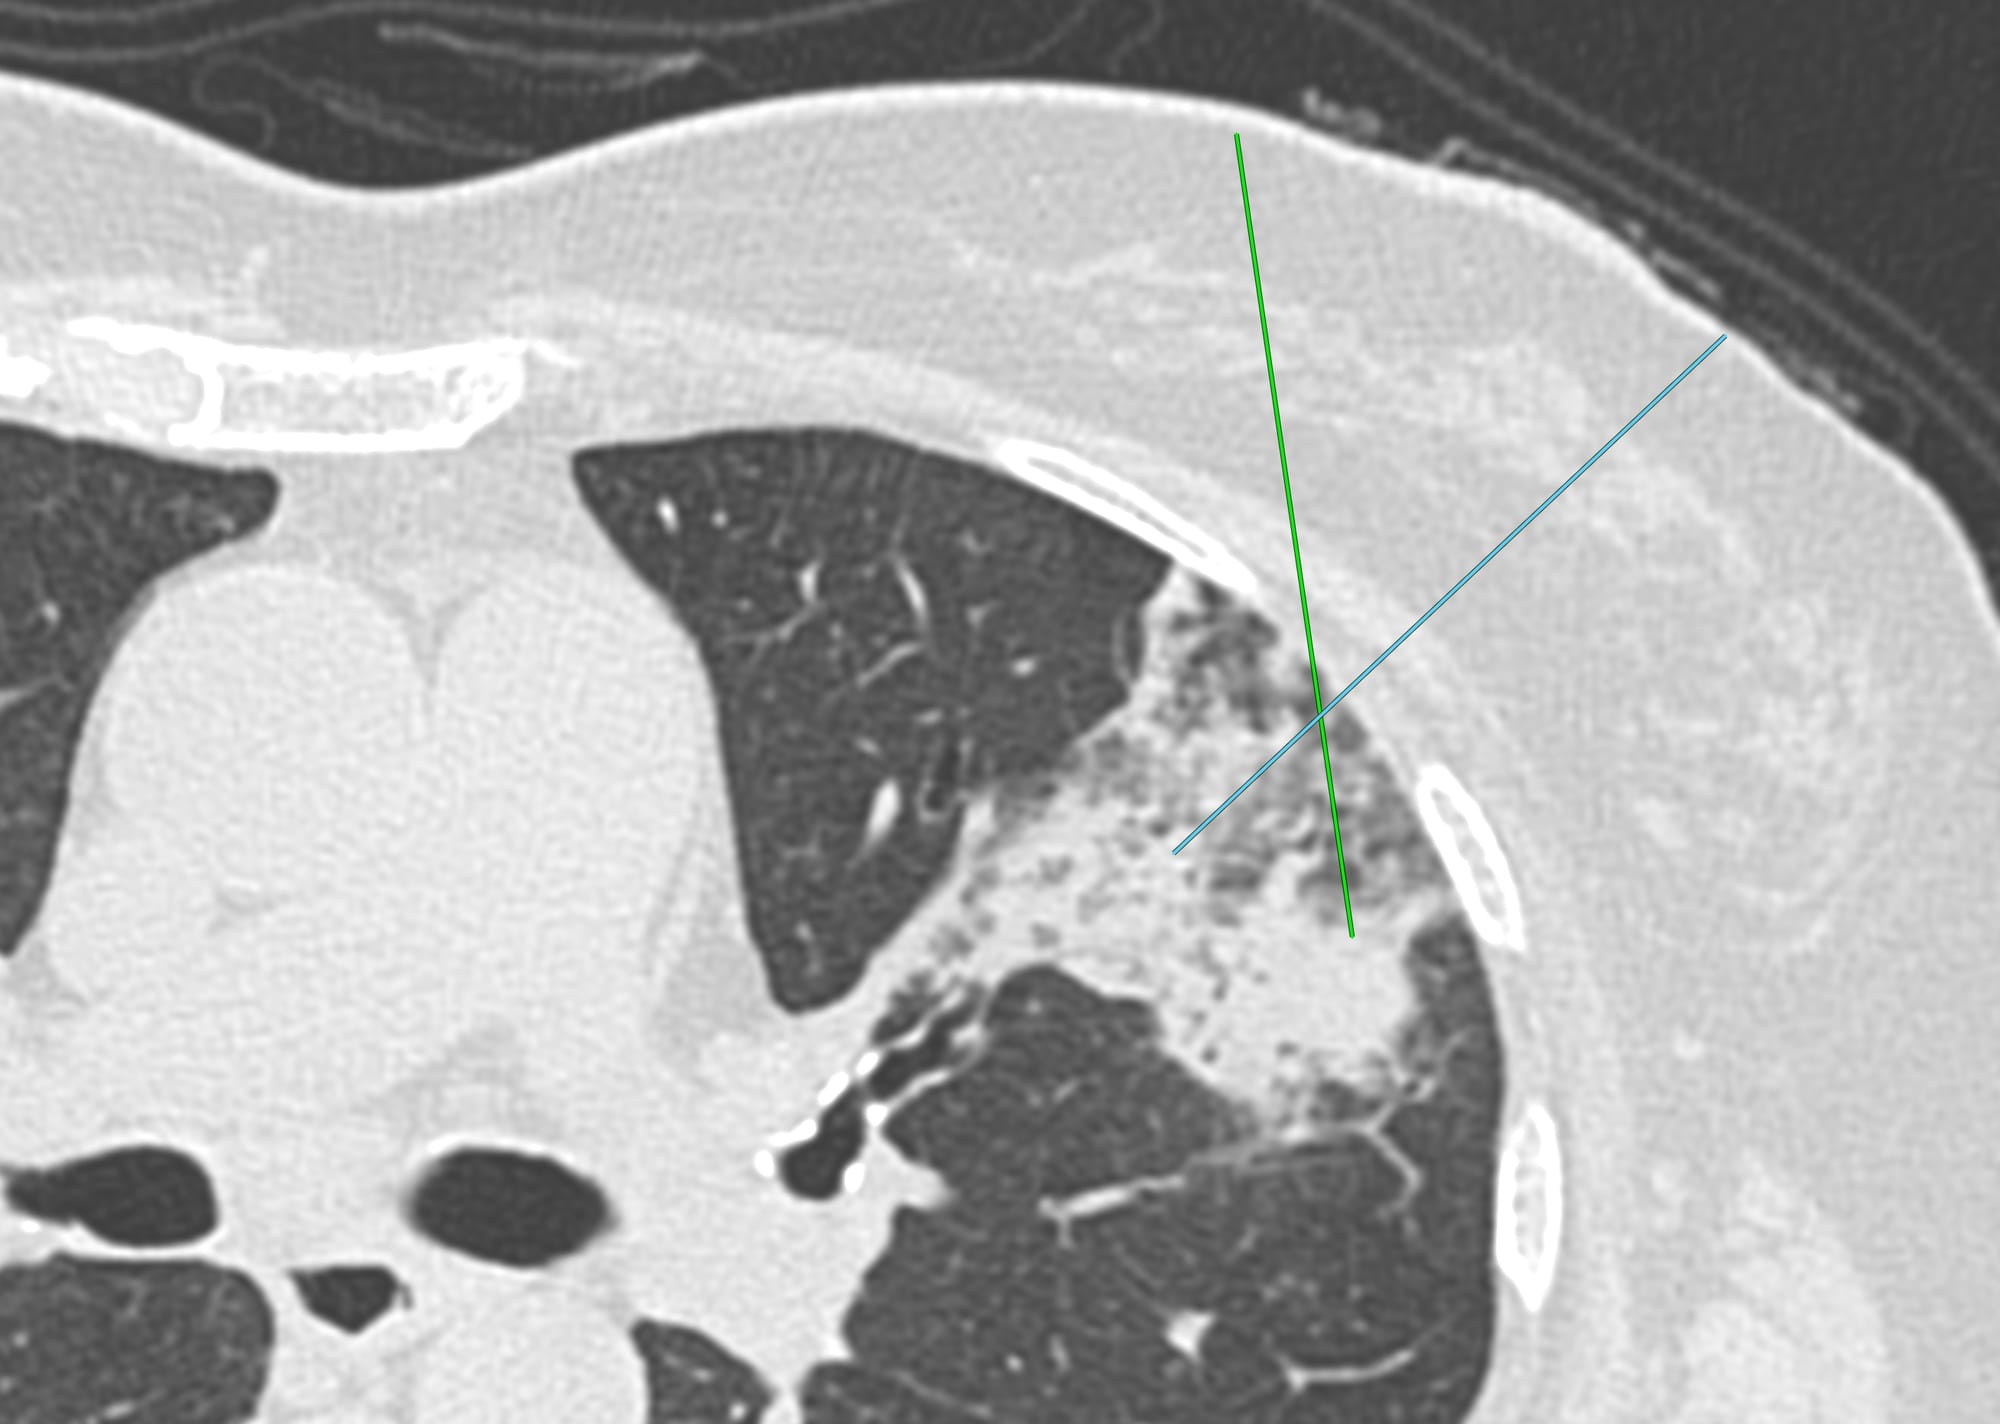

Current Case:

59-years old with fever and non-resolving consolidation

What would be your approach?

The video below describes the case and the reason for performing a biopsy parallel to the vessels and not perpendicular